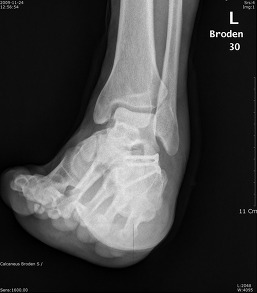

Broden view

촬영목적 : Subtalar joint의 골절시(comminuted fracture) 관절의 관련 여부를 관찰

촬영자세 : Supine 자세로 다리와 카세트 중앙은 일치하도록 하며,internal oblique자세에서 발목관절이 90˚ 굽힌상태를 유지하도록 발을등쪽으로 굽힌다.

중심선 :  cephalic 10˚ ,20˚, 30˚, 40˚ 로  Lateral malleolar에서 아래앞쪽으로 2~3Cm 떨어진지점에 입사한다

촬영Point : Subtalar Joint가 열려져 나타나며,10˚에서는 뒤쪽관절면의 뒷부분,20˚~30˚에서는 Sustentaculum(재거돌기)과 talus(거골)사이의 관절,40˚에서는 앞부분이 잘나타나야한다.